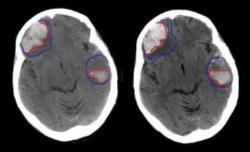

3 عامل که خطر سکته مغزی را کاهش می دهد

آنها 350 آزمایش مرتبط با تحقیقات خود را شناسایی کردند. این آزمایشها، مدیریت بیماری هایی مانند بیماری قلبی، توانبخشی سکته مغزی، نارسایی قلبی و پیش دیابتی را مورد کاوش قرار داده بودند.

داروهای موسوم به ادرار آور برنده اصلی برای بیماران مبتلا به نارسایی قلبی هستند در حالی که ورزش بهترین گزینه برای بیماران مبتلا به سکته مغزی در زمینه افزایش امید به زندگی است.

پژوهشگران بر این عقیده اند که برداشتن گام های مهمی مانند ورزش منظم، رعایت یک رژیم غذایی متعادل و ترک کردن سیگار می تواند خطر بروز سکته مغزی را به طور قابل توجهی کاهش داد.

فعالیت بدنی متوسط می تواند خطر بروز سکته مغزی را تا 27 درصد کاهش دهد.